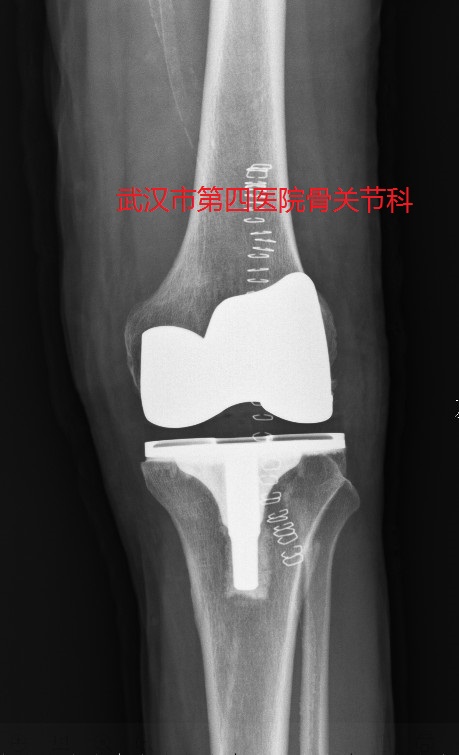

4.全膝关节置换术:对于晚期的多间室关节炎,尤其是伴有多种畸形时,考虑全膝关节置换术。

全膝关节置换术